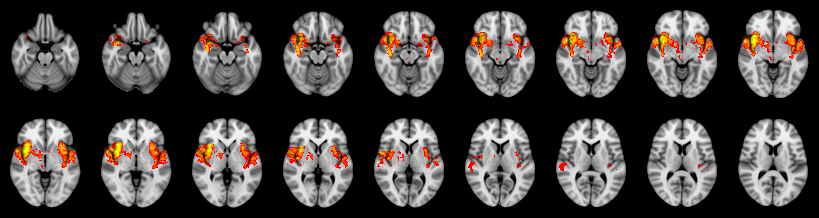

Combined

Stouffer:

Edgington: